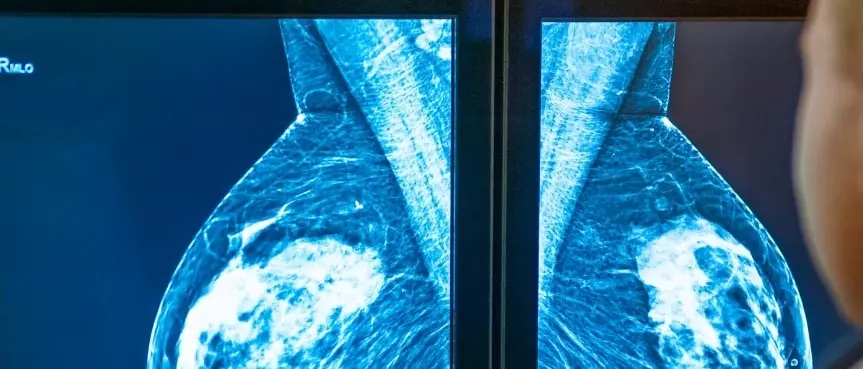

La regione risulta ultima in Italia nelle campagne di prevenzione contro i tumori. A pesare è soprattutto la disorganizzazione del pubblico che non riesce a coinvolgere la popolazione target ma c’è anche una sottovalutazione del rischio. Al Sud in molti pensano di non aver bisogno di monitorarsi

La consigliera regionale Pd analizza la situazione sanitaria nel Catanzarese e denuncia: «A Lamezia il reparto di anatomia patologica rischia la chiusura. Gli screening mammografici? Insufficienti»